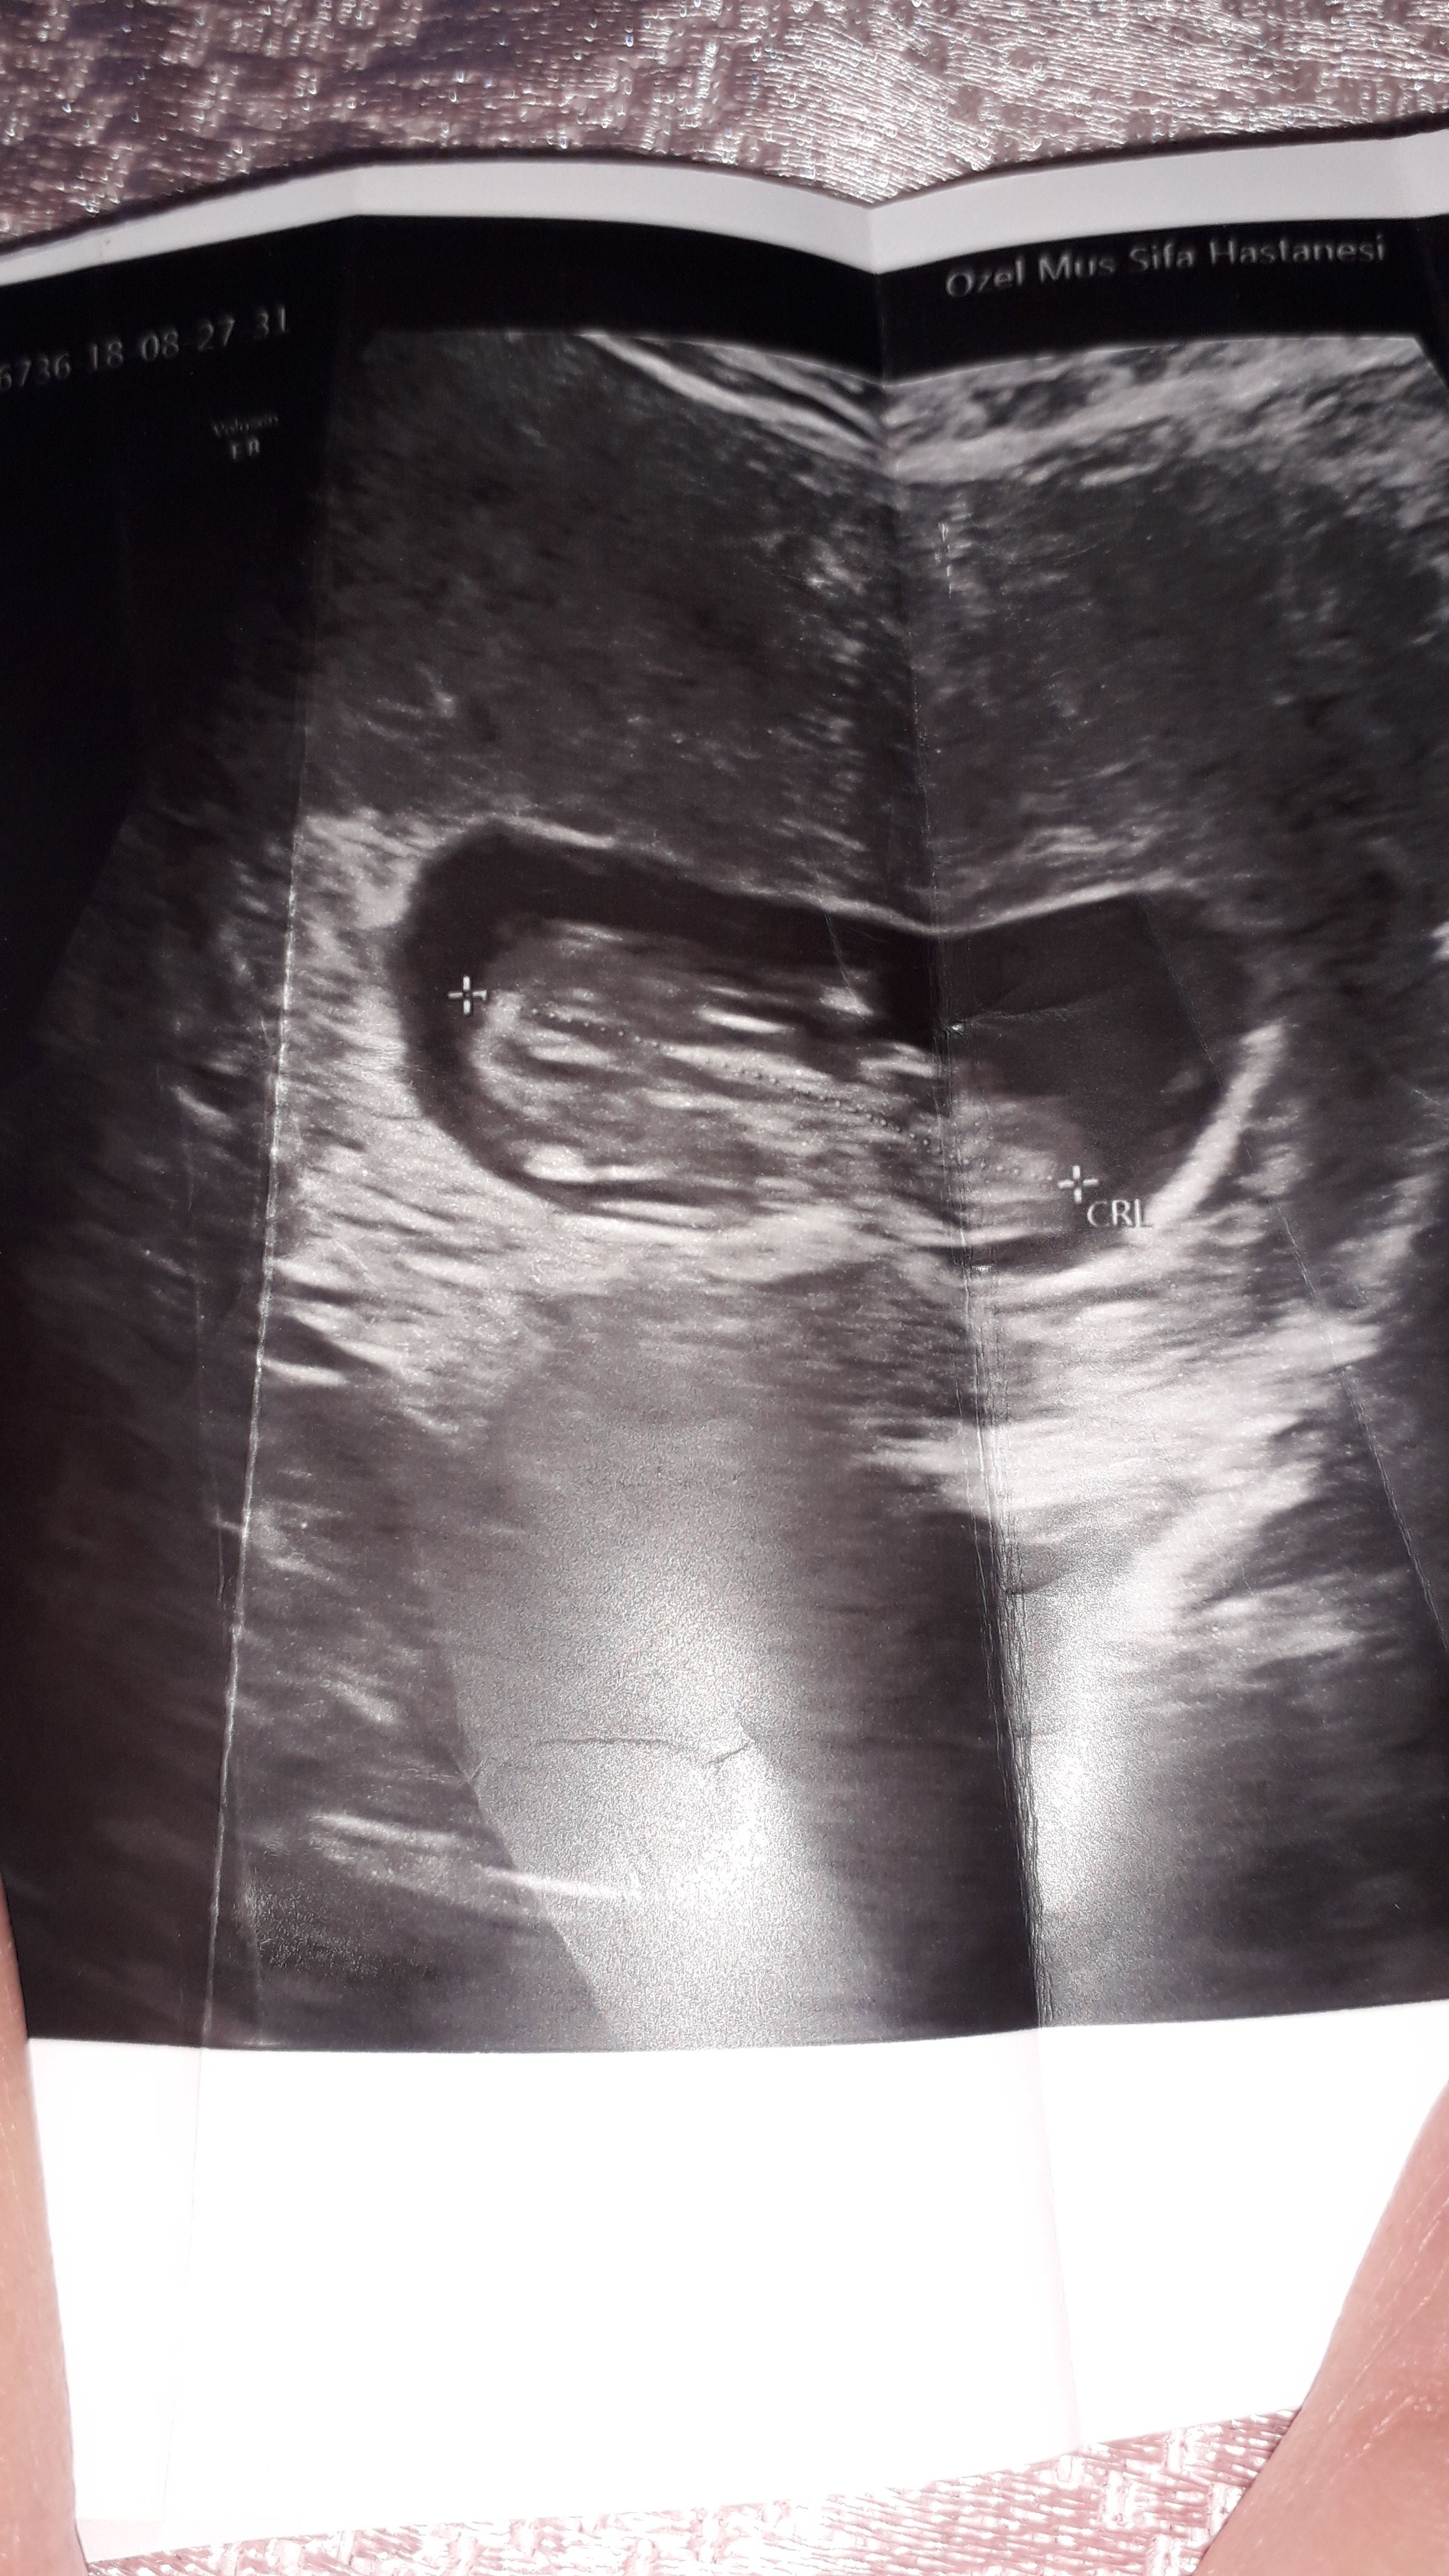

Merhaba ,

Nub teorisiyle cinsiyeti uzman hekimler belirleyebiliyormuş. Bu yüzden doğruluk payı var.

Nub teorisi ile ilgili istatistiki bilgiler şöyledir;

1 hafta sonunda, doğruluk oranı 48 yüzde olduğu

12 hafta sonunda, doğruluk oranı 91 yüzde olduğu

13 hafta sonunda, doğruluk oranı 94 yüzde olduğu